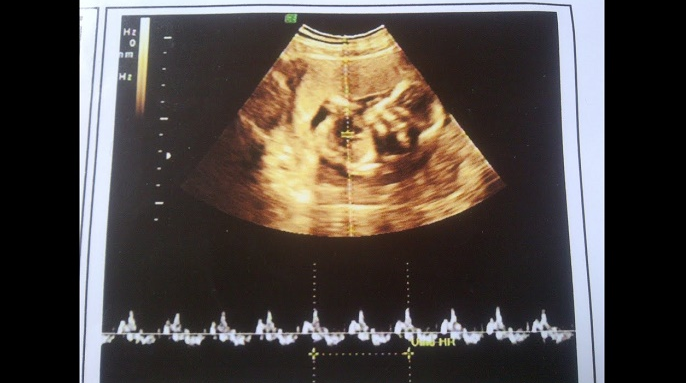

Khi mẹ bầu bước sang tuần thai thứ 7 sẽ bắt đầu đi siêu âm thai lần đầu tiên. Việc siêu âm thai lúc này giúp xác định phôi phát triển ổn định hay không và theo dõi sự phát triển bước đầu của thai nhi. Vậy qua hình ảnh siêu âm thai 7 tuần tuổi, mẹ sẽ biết được những thông tin gì về thai nhi?

Trước khi tìm hiểu về hình ảnh siêu âm thai nhi 7 tuần tuổi, bạn nên hiểu rõ tầm quan trọng của việc siêu âm vào giai đoan này. Thời điểm từ tuần thứ 7 đến tuần thứ 10 của thai kỳ rất thích hợp để siêu âm thai mà các mẹ bầu không được bỏ qua. Vì khi siêu âm vào thời điểm này sẽ tính được tuổi thai nhi chính xác nhất do thai nhi đã hình thành. Theo dõi phôi thai rất quan trọng vì đó là yếu tố xác định đặc điểm phát triển của thai nhi tại giai đoạn này.

Để tiến hành siêu âm thai 7 tuần tuổi, có hai phương pháp là siêu âm ổ bụng và siêu âm đầu dò. Thông thường bác sĩ sẽ chọn phương pháp siêu âm ổ bụng. Tuy nhiên, có thể bác sĩ sẽ siêu âm đầu dò nếu thai còn quá nhỏ hay lớp mỡ bụng của mẹ dày. Thường kết quả cũng như hình ảnh siêu âm thai 7 tuần tuổi bằng siêu âm đầu dò sẽ chính xác hơn.

Khi mẹ đi khám thai và siêu âm trong giai đoạn thai nhi 7 tuần tuổi, hình ảnh siêu âm thai 7 tuần tuổi cho thấy bé bắt đầu phát triển và hình thành các bộ phận cơ thể như sau:

Tóm lại, khi thai 7 tuần tuổi là giai đoạn thai nhi bắt đầu phát triển rõ rệt và mẹ cần đi khám thai và siêu âm tại thời điểm này. Hình ảnh siêu âm thai 7 tuần tuổi cho biết sự hình thành của các cơ quan trong cơ thể thai nhi, nghe nhịp tim thai nếu có cũng như phát hiện những dấu hiệu bất thường ở mẹ và bé.